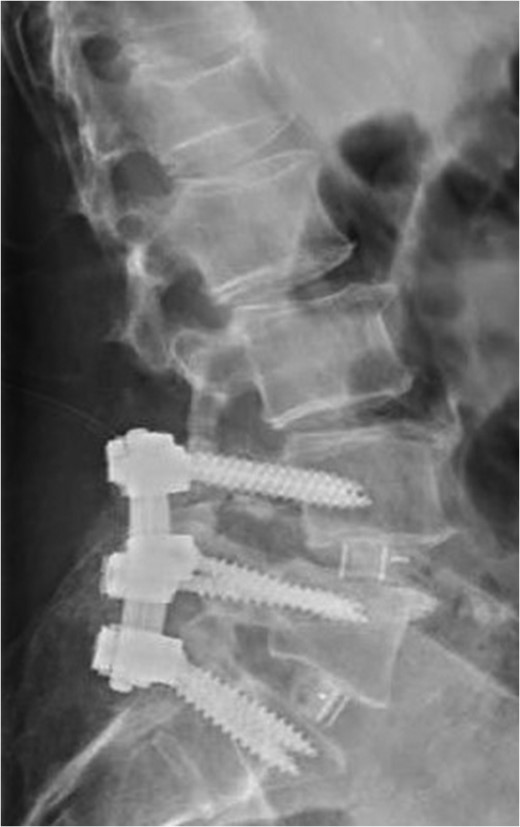

Standing lateral lumbar radiograph obtained 2 weeks following the patient's initial lumbar surgery (L3–S1 laminectomy). No instability is noted on the postoperative image.